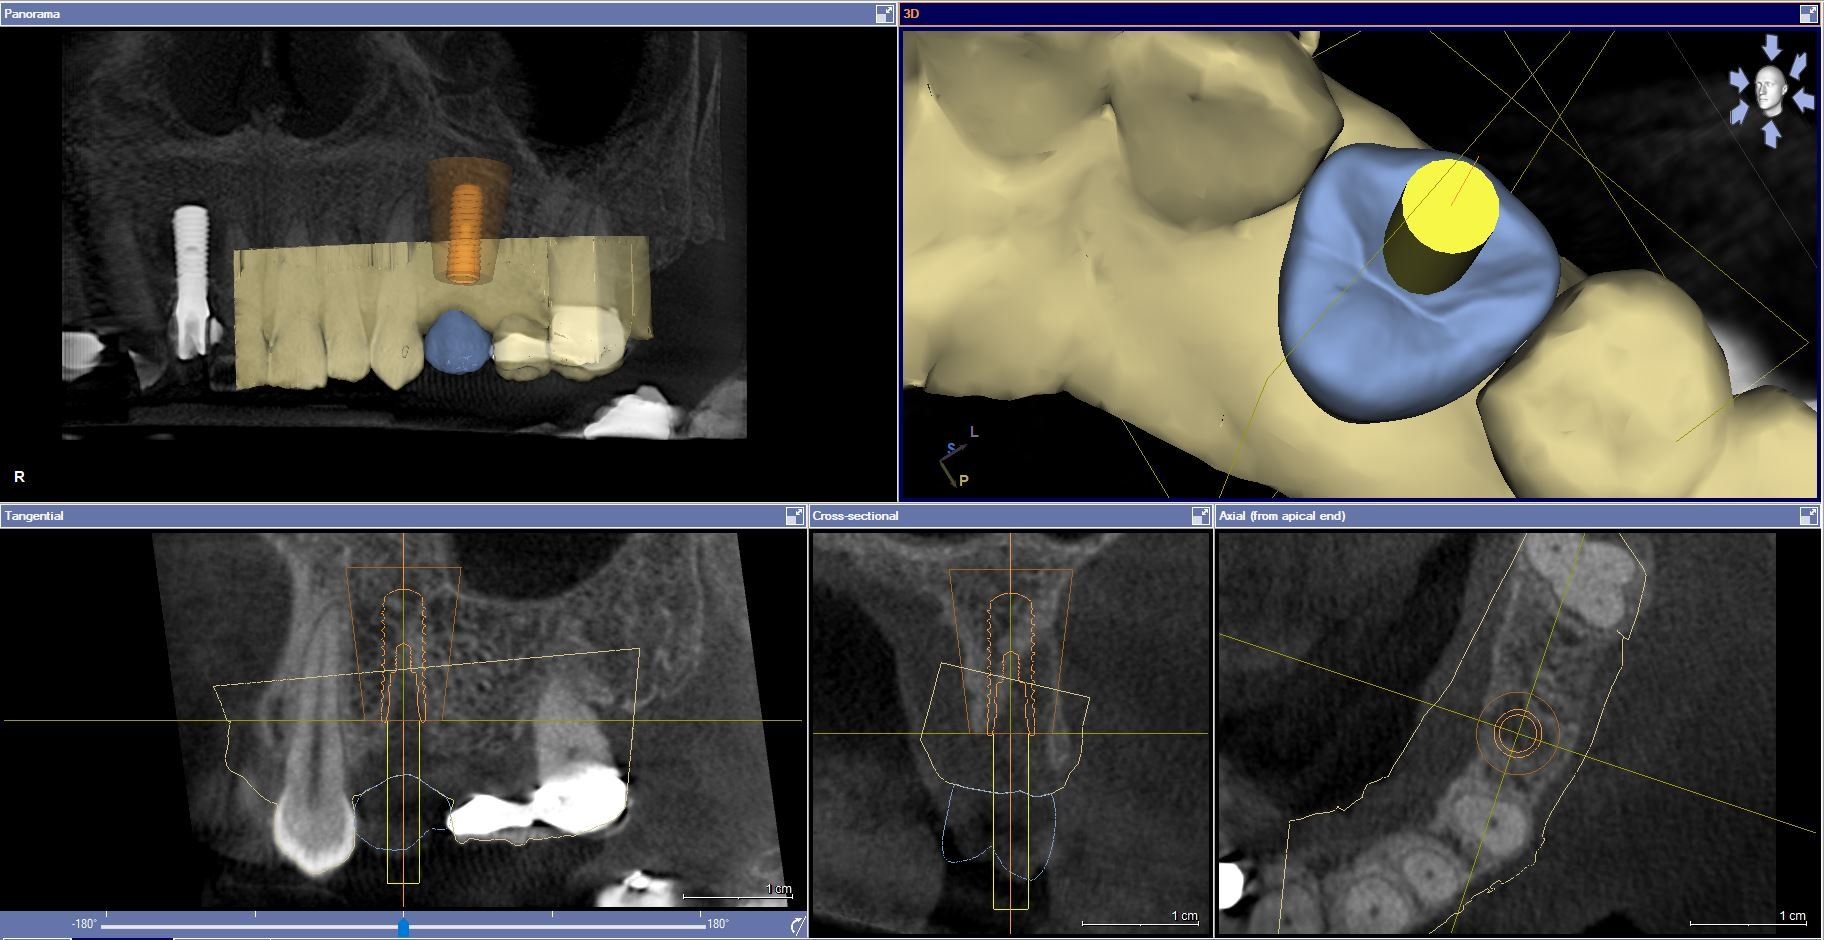

From simple x-rays and cbct datasets, to implant guides and placements.